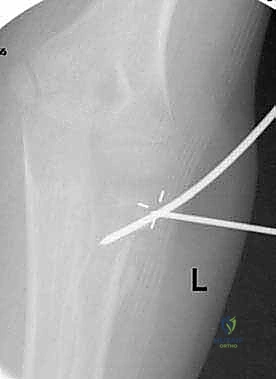

متابعة دقيقة لمراحل التئام العظم بعد الرد والتثبيت لضمان استعادة الشكل التشريحي.

* إذا كان العظم مستقراً بعد الرد، يتم وضع جبس. إذا كان غير مستقر ويميل للعودة لوضع الكسر، يتم الانتقال فوراً للتثبيت.

* يتم استخدام طرف المسمار المنحني كـ "أداة دفع" لرفع رأس الكعبرة المكسور وإعادته إلى مكانه التشريحي الصحيح بدقة متناهية تحت جهاز الأشعة (C-arm).

صورة توضح دخول المسمار المرن عبر التجويف النخاعي لرد الكسر من الداخل دون المساس بمفصل المرفق.